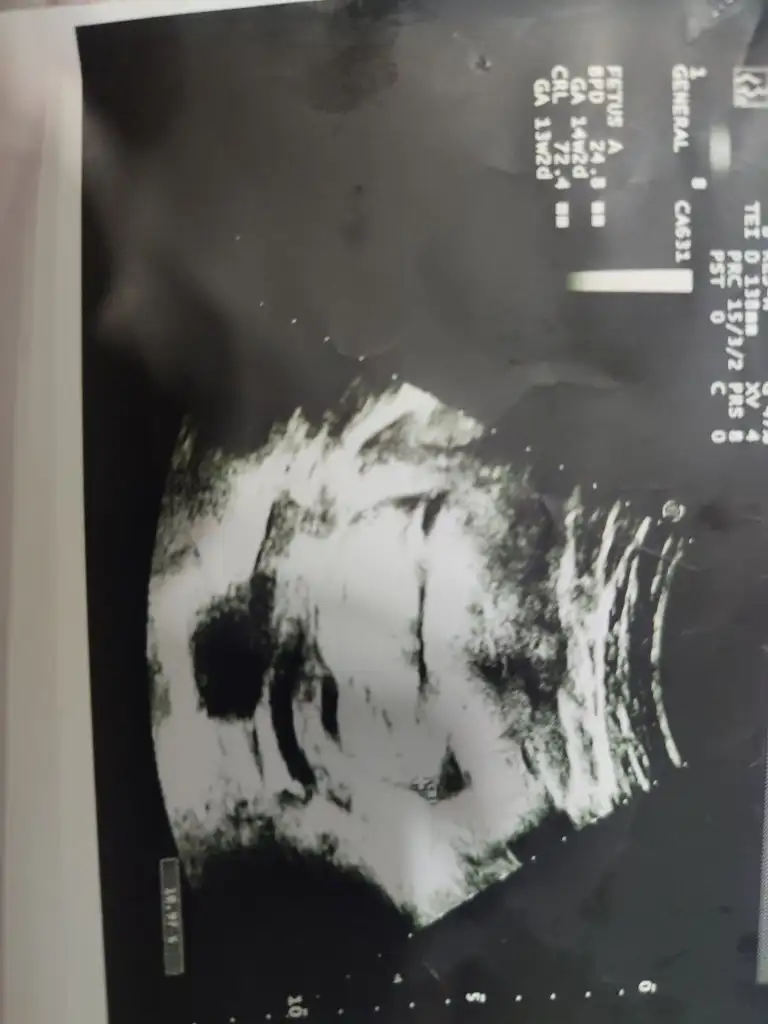

12+6 ydı bir hafta geç döllenme aslında 13+5 olması lazımdı 😂 karından ultrason